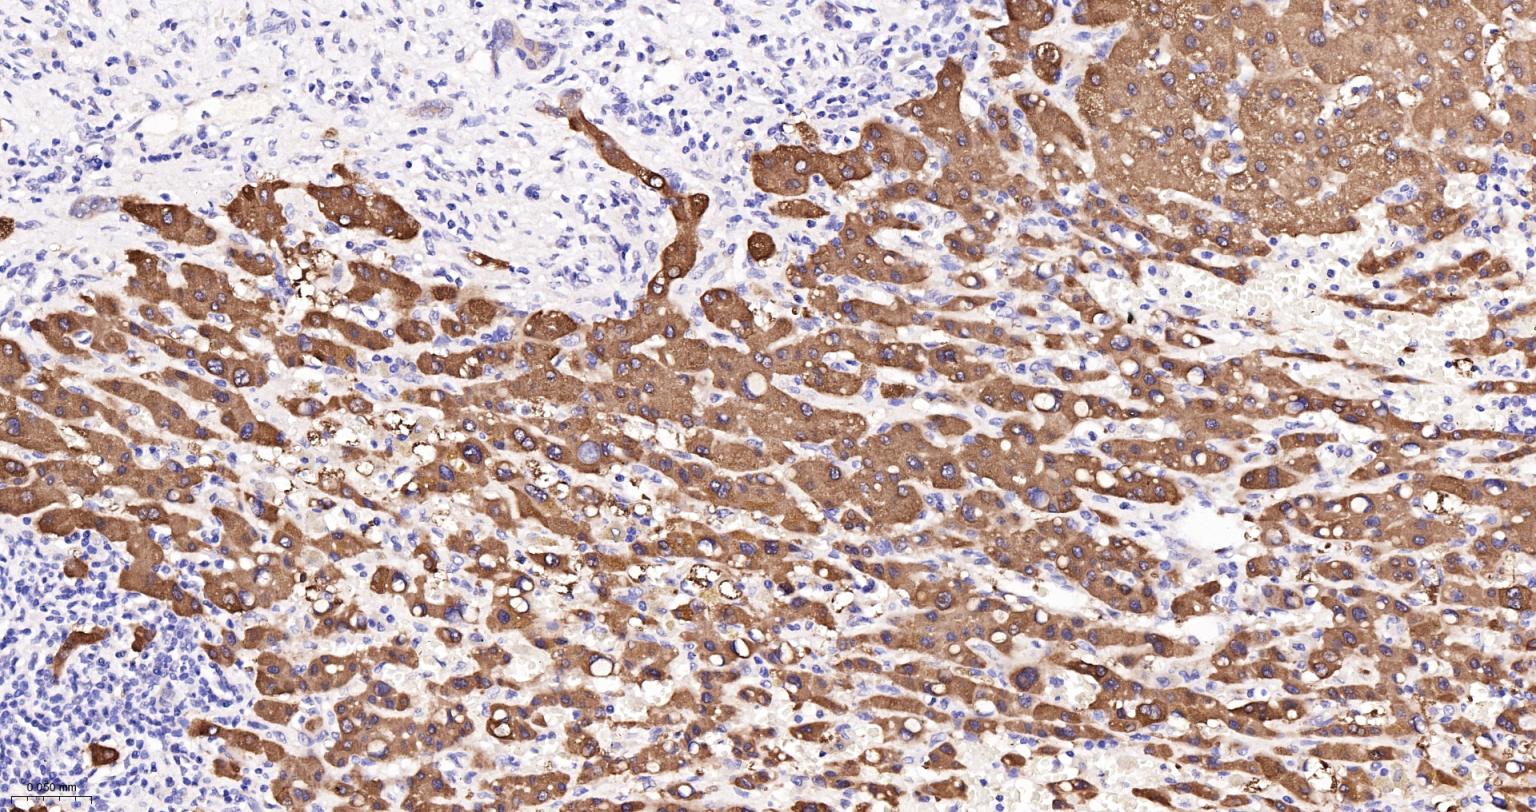

Paraformaldehyde-fixed, paraffin embedded Human Liver Cancer; Antigen retrieval by boiling in sodium citrate buffer (pH6.0) for 15 min; The section was incubated with FTCD Monoclonal Antibody, Unconjugated (bsm-61401R) at 1:200 overnight at 4°C, followed by conjugation to the bs-0295G-HRP and DAB (C-0010) staining.